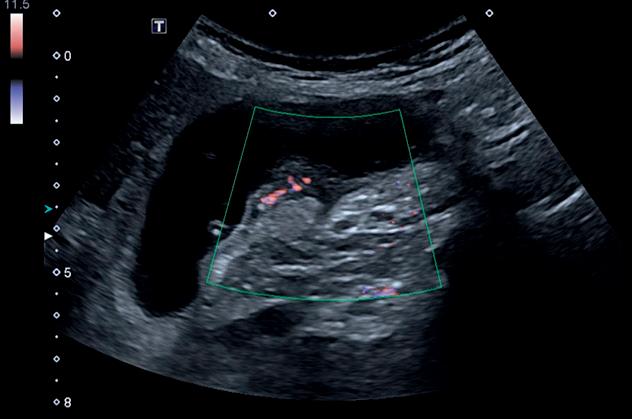

Fig. 2-18. Nódulo na bexiga com vascularização ao Doppler.